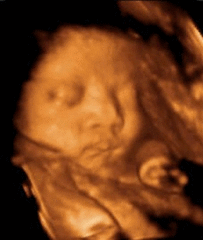

首先,四维彩超可以更加清晰地观察胎儿的发育情况,及时发现一些异常情况。通过四维彩超可以看到胎儿的面部特征、四肢动作等,有助于医生判断胎儿是否有先天性畸形。这对于早期发现并治疗胎儿异常是非常有帮助的。

其次,四维彩超可以帮助医生检查胎儿的器官是否正常发育。通过四维彩超可以看到胎儿心脏、脑部、肾脏等器官的情况,及时发现问题并采取相应措施。这对于预防和治疗胎儿畸形起到了积极的作用。